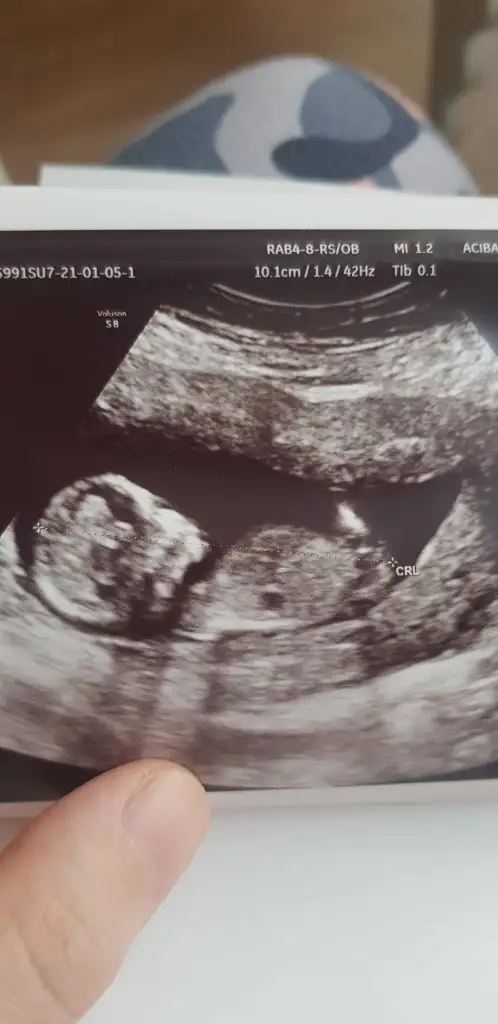

Ikra meyra merhaba canım bana da yorum yapar mısın 12+3

Evet kız görünüyor